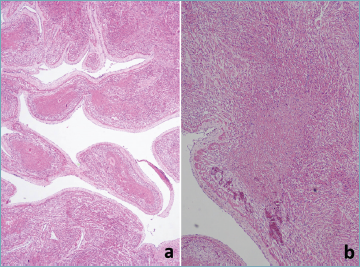

Microscopic examination of the heart revealed myocardial coagulative necrosis in areas corresponding to macroscopic color inhomogeneity (Fig. 2). Calcification of the internal elastic lamina was observed in the aortic arch and in both large and intraparenchymal medium-sized coronary arteries, with complete occlusion of the smallest coronary branches (Fig. 3). In the lungs, calcifications affected both the afferent arteries and the intraparenchymal arterioles (Fig. 4). In the intestine, kidneys, adrenal glands, spleen, thymus, and pancreas, calcifications were confined exclusively to the afferent/extra-parenchymal arteries (Fig. 5). The brain and liver appeared uninvolved; however, calcification of the larger vessels supplying these organs cannot be ruled out. The veins were unaffected. There was no evidence of atherosclerosis, thrombi, inflammatory changes, or emboli. No extravascular calcifications were detected. As far as could be assessed, no evident ischemic damage was observed in these organs. Microscopic evaluation of the liver confirmed advanced fibrosis progressing to cirrhosis, corresponding to stage 4 fibrosis according to the METAVIR scoring system. The hepatic architecture was disrupted by numerous regenerative nodules encircled by fibrous septa. Prominent ductular proliferation was observed. There was no histological evidence of biliary stasis or intracellular accumulation of fat or glycogen within the hepatocytes. Iron staining was not sufficiently conclusive to support a suspicion of hemochromatosis. Extramedullary hematopoiesis was noted, consistent with the patient’s age (Fig. 6).

Figure 6. Microscopic evaluation of the liver confirmed the presence of extensive fibrosis with architectural distortion and nodular formation, indicative of progression toward cirrhosis. PAS and Perls stains showed no evidence of glycogen or iron deposition. a: hematoxylin-eosin, b: trichrome, c: PAS, d: Perls, original magnification 4× (a-d).